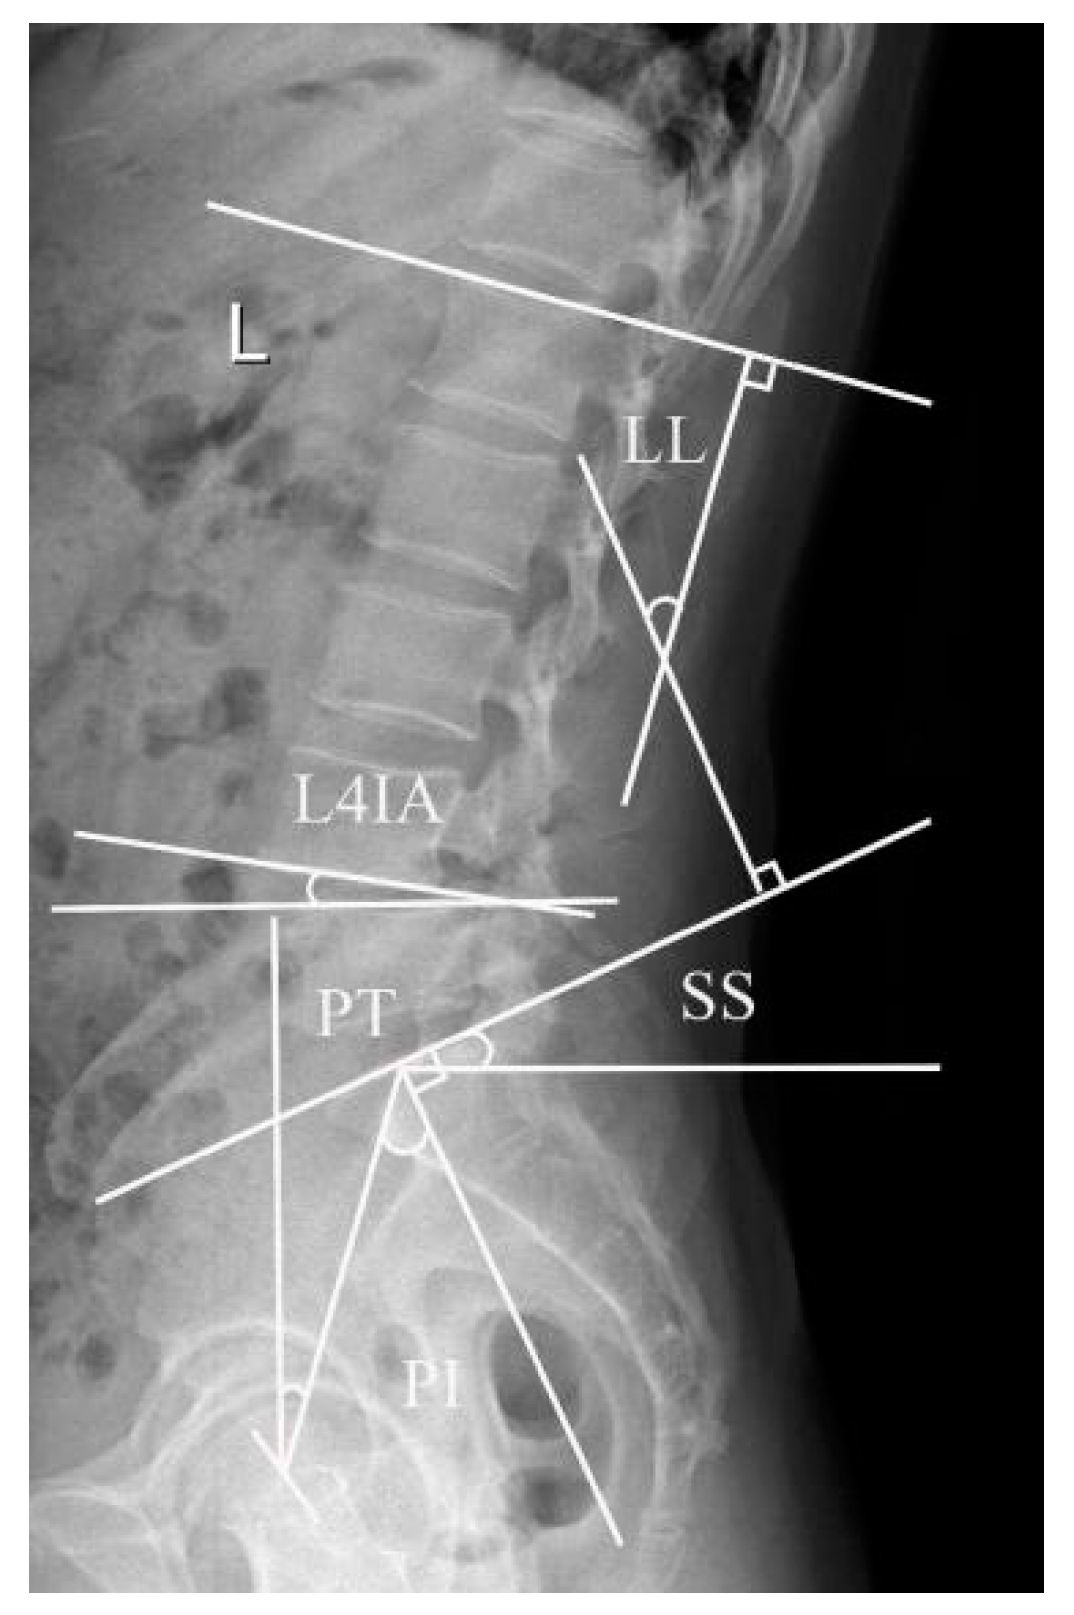

Lumbar lordosis (LL): The sagittal angle between the L1 upper endplate and the tangent of the S1 upper endplate. L4 inclination angle (L4IA): The intersection between the tangent line and the horizontal line at the lower margin of the fourth lumbar vertebra. Pelvic incidence (PI): The angle between the perpendicular to the upper sacral endplate at its midpoint and the line connecting this point to the femoral head axis. This is a morphological parameter that is considered to be a constant and has nothing to do with the spatial orientation of the pelvis. Sacral slope (SS): The angle between the horizontal and the upper sacral endplate. It is a positional parameter, which varies according to the pelvis position. Pelvic tilt (PT): The angle between the vertical and the line passing through the midpoint of the sacral plate to the axis of the femoral head. It is also a position parameter (Figure 1).

Figure 1.

This illustration displays the pelvic incidence (PI), the sacral slope (SS), the pelvic tilt (PT), the lumbar lordosis (LL), and the L4 inclination angle (L4IA).